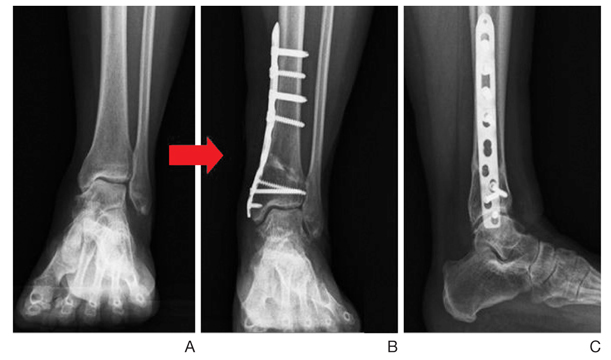

Οστεοτομία κνήμης

Η επέμβαση αυτά αλλάζει τον τρόπο που φορτίζεται η άρθρωση κατά τη στάση, τη βάδιση και γενικά τη δραστηριότητα. Έχει ένδειξη σε σχετικά νέους ασθενείς, στους οποίους η αρθρίτιδα είναι αποτέλεσμα αστάθειας με βαθμιαία παραμόρφωση σε ραιβότητα (το άκρο πόδι είναι στραμμένο προς τα μέσα), καθώς και σε αρθρίτιδα συνέπεια κατάγματος. Είναι αποτελεσματική εφόσον η ‘μισή’ περίπου άρθρωση έχει φυσιολογικό χόνδρο. Για την επιβεβαίωση της ένδειξης μπορεί να συνδυαστεί με αρθροσκόπηση. Πρόκειται για κόψιμο του οστού (οστεοτομία) στο κάτω άκρο της κνήμης και οστεοσύνθεση σε διαφορετική θέση, ώστε να αλλάξει ο άξονας φόρτισης όλου του σκέλους και να μην περνάει από την περιοχή της άρθρωσης που έχει βλάβη ο χόνδρος. Προκαλούμε δηλαδή ένα ΄τεχνητό κάταγμα’ στο επιθυμητό επίπεδο και το βάζουμε να ‘κολλήσει’ σε άλλη θέση, τέτοια που να διορθώσουμε τον άξονα της άρθρωσης (που έχει βλαφτεί από την αρθρίτιδα). Η συγκράτηση του οστού (οστεοσύνθεση) γίνεται είτε με πλάκα και βίδες εσωτερικά (σ’ αυτή την περίπτωση χρησιμοποιούμε γύψο για 3 μήνες μετεγχειρητικά), είτε με εξωτερική οστεοσύνθεση. Η οστεοτομία έχει σκοπό να διατηρήσει την κίνηση στη φυσική άρθρωση και να ΄κερδίσει χρόνο’ πριν χρειαστεί μια πιο ‘ριζική’ επέμβαση. Στόχος είναι να ελαττωθεί ο πόνος και να επιβραδυνθεί η εξέλιξη της οστεοαρθρίτιδας. Ανάλογα με το πόσο προχωρημένη είναι η αρθρίτιδα, η οστεοτομία είναι δυνατό να δώσει καλά αποτελέσματα σε νέους και δραστήριους ασθενείς για αρκετά χρόνια.